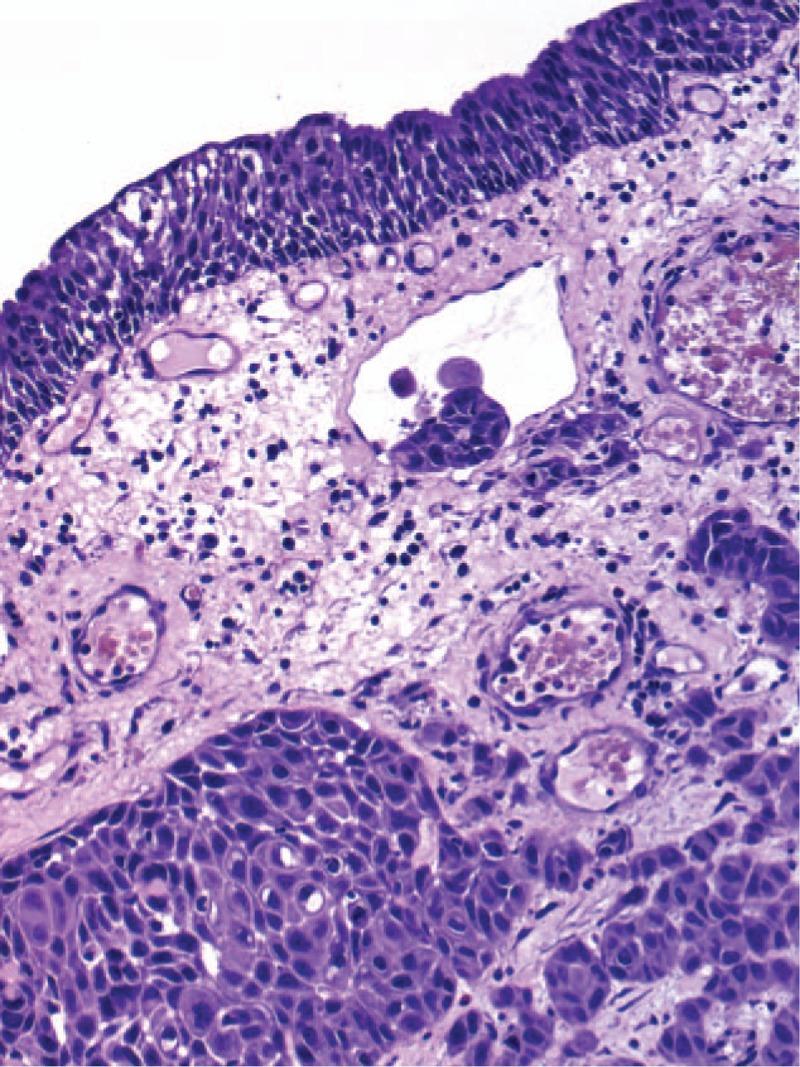

Primary vaginal squamous cell carcinoma (SCC) is a rare disease. Primary SCC in prolapsed vagina is extremely rare. In the presented case additional bladder involvement was found.

Diagnosis was confirmed by the vaginal ulceration biopsy and cystoscopic biopsy of the involved bladder.

Primary SCC mimicking decubitus which appeared in prolapsed vagina, may be accompanied by bladder involvement.

原发性阴道鳞状细胞癌(SCC)是一种罕见疾病。脱垂阴道中的原发性SCC极为罕见。在本病例中,发现了额外的膀胱受累情况。

通过阴道溃疡活检和受累膀胱的膀胱镜活检确诊。

模仿脱垂阴道中褥疮出现的原发性SCC,可能伴有膀胱受累。